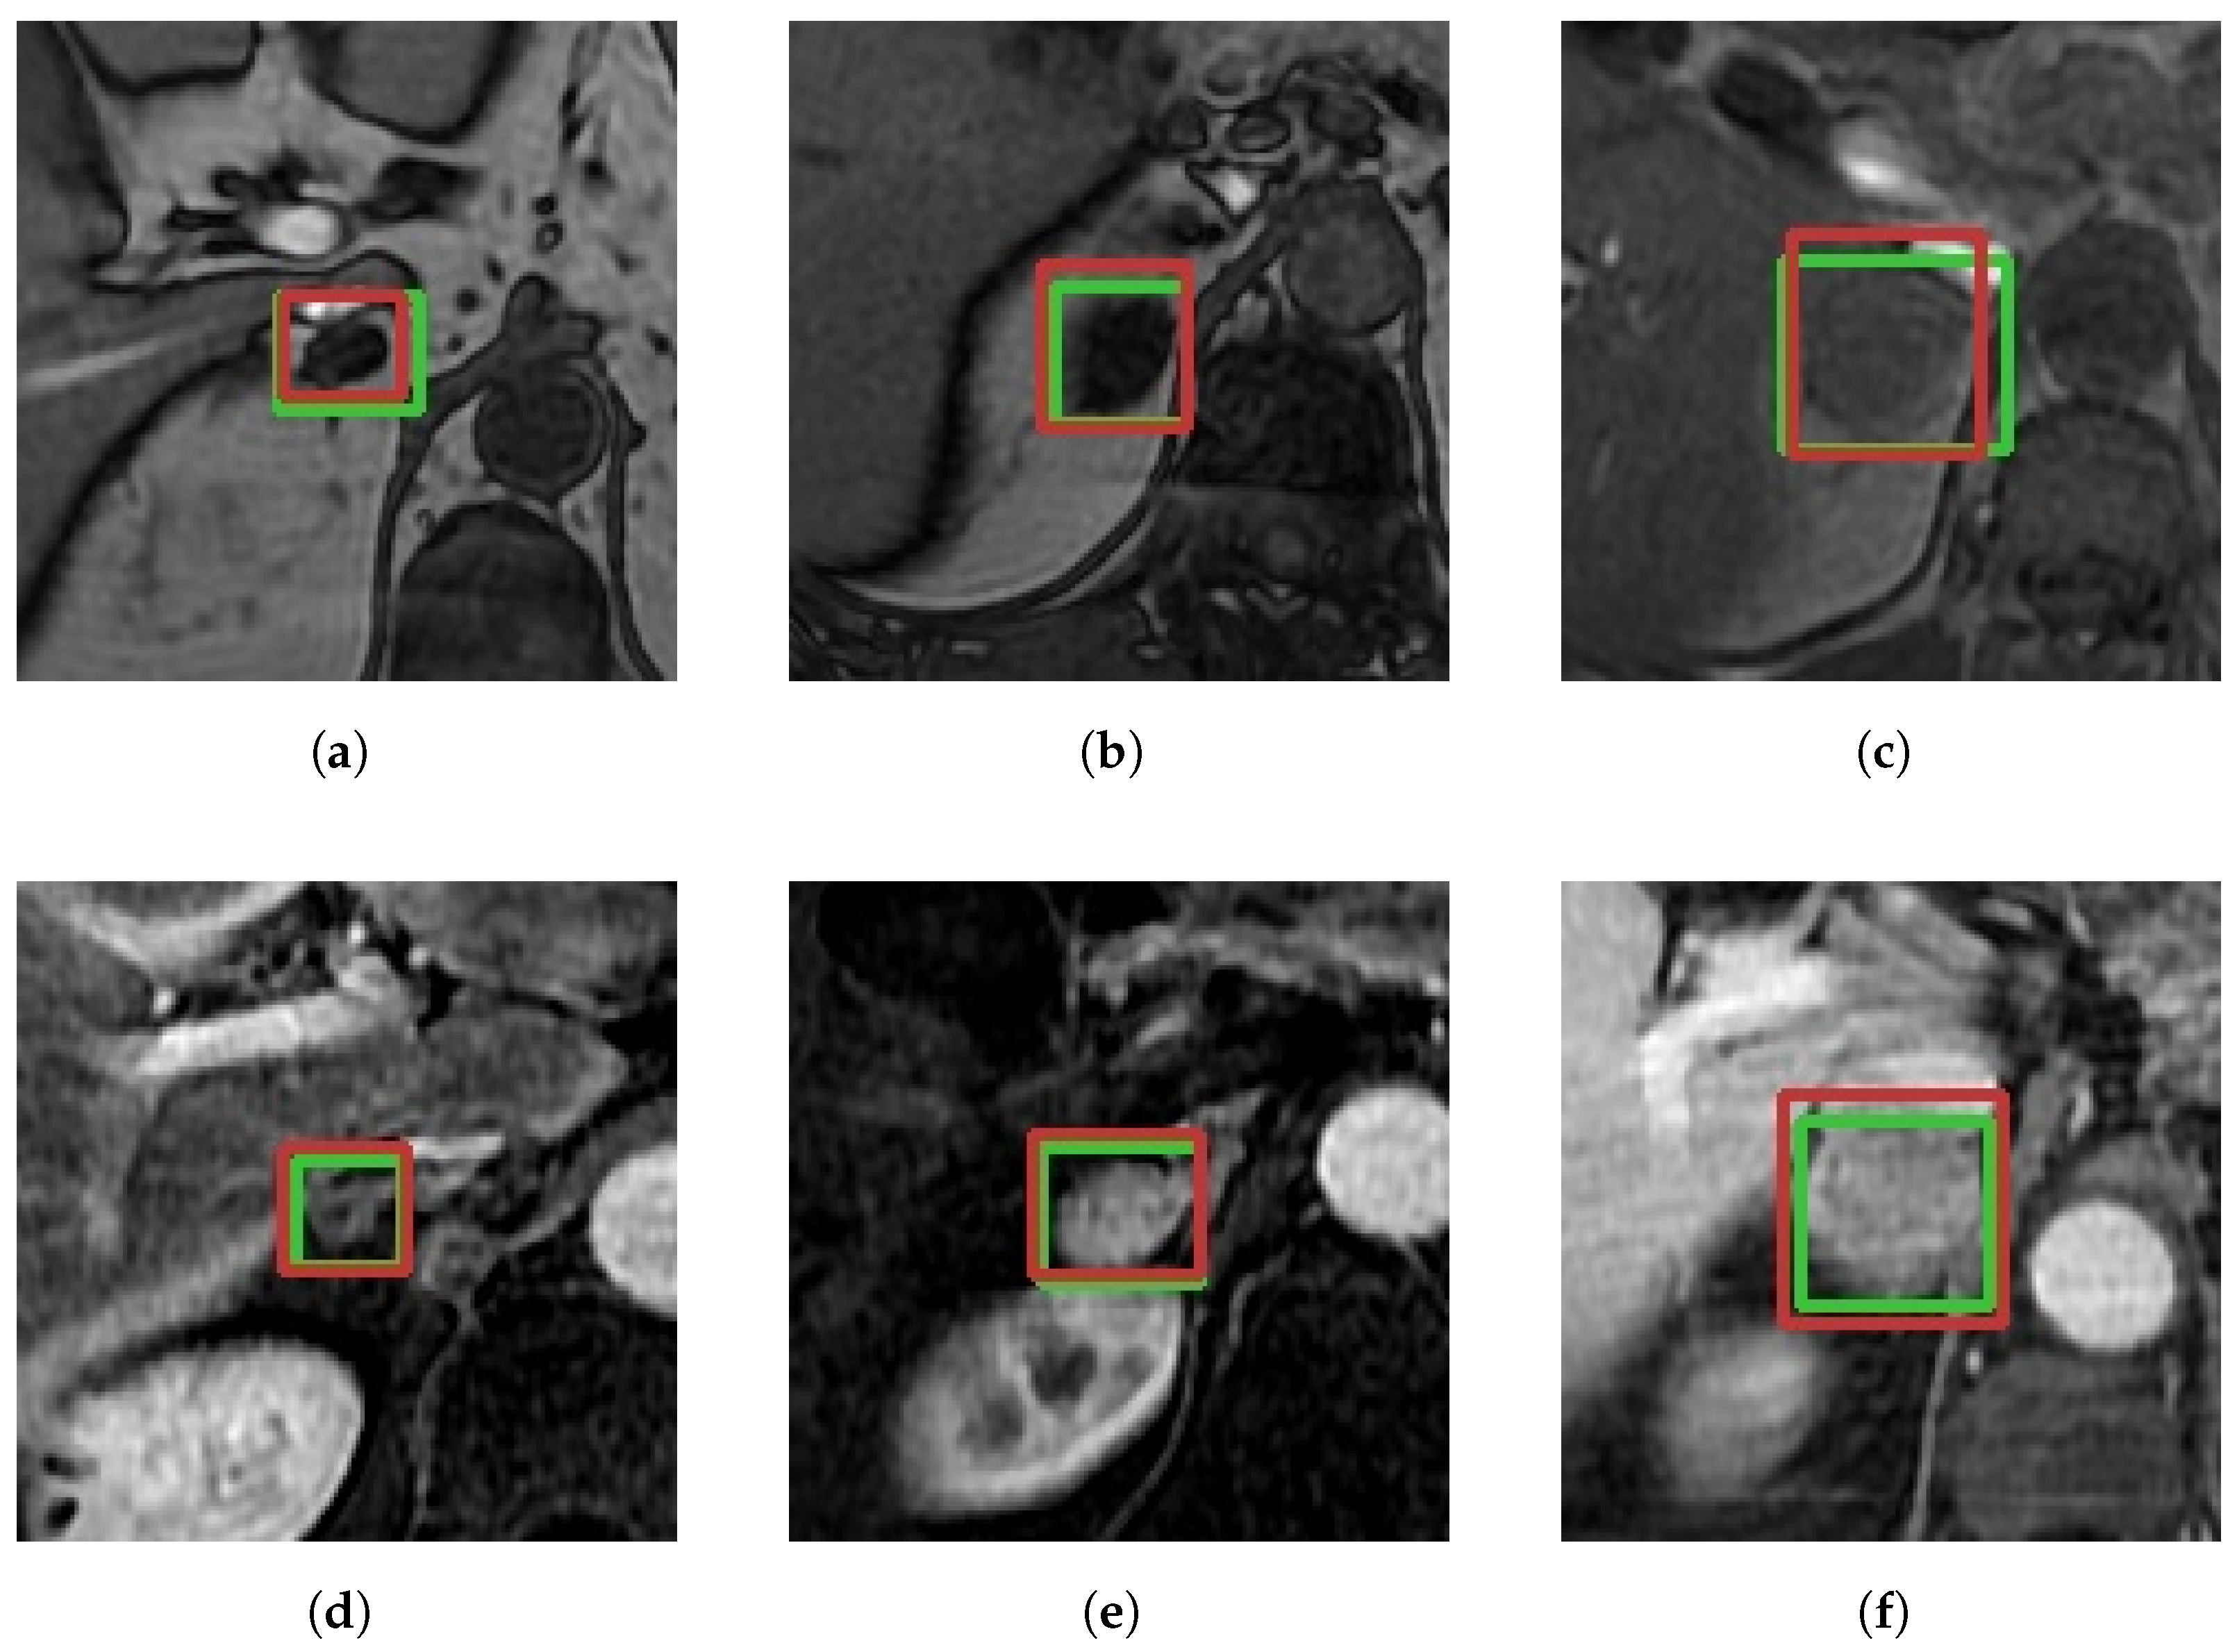

In addition to presenting the quantitative results of our pipeline, it is essential to highlight qualitative examples of its performance. Figure 3 showcases correct detections and classifications of adenomas across different patients, highlighting the diversity in adenoma sizes, shapes, and imaging characteristics. The first row of the figure shows T1-W CS OOP slices and the second row presents T1-W CE slices. The green bounding boxes represent the medical annotations and the red boxes represent the model’s predictions.

Notably, the model successfully identifies very small adenomas (e.g., Figure 3a,d) with more elongated, horizontal shapes, and larger adenomas with more square-like shapes (e.g., Figure 3c,f). Furthermore, the pipeline’s robustness in handling variations in image intensity is evident, highlighting its capacity to adapt to diverse imaging conditions, including contrast-enhanced and non-contrast-enhanced sequences.

Figure 3. Examples of true positive detections for adenomas across different MRI sequences and different patients. Each row corresponds to a different MRI sequence: the first row shows T1-Weighted Chemical Shift (Out-of-Phase) images, and the second row shows T1-Weighted Contrast-Enhanced images. Green bounding boxes are the ground truth; red is the high-score prediction. Subfigures are labeled (af) for reference.